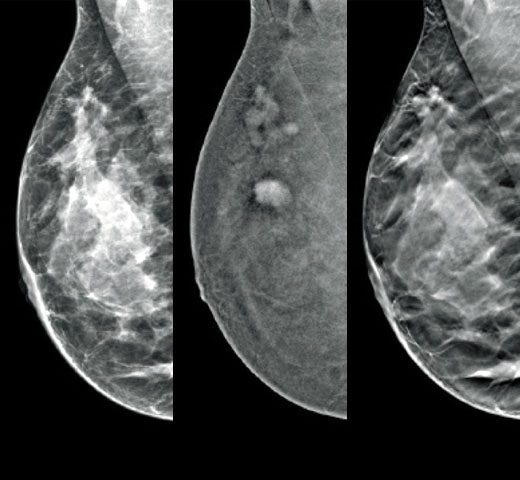

Higher breast density is known to increase a woman’s risk for breast cancer.1 The need for accurate, unbiased analysis is therefore critical. Powered by machine learning, Quantra technology software analyses both 2D™ and tomosynthesis images for distribution and texture of parenchymal tissue. It categorises breasts in four breast composition categories consistent with guidance from the American College of Radiology (ACR) BI-RADS Atlas 5th Edition.2

In addition to volume, pattern and texture of fibroglandular tissue may play just as an important role in mammographic cancer risk prediction.3-5 By analysing and categorising breast texture and pattern, our technology can deliver the accurate information you need to achieve more consistent and reliable scoring and confidently design patient-specific screening.

Objective machine learning algorithm that assigns breast density category based on analysis of breast tissue texture and patterns.

Breast imaging scans